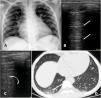

A 10-year-old girl with homozygous SCD checked in at the hospital with neck pain starting 8 h before admission. She had a past history of multiple hospitalizations due to painful VOC and ACS, for which she started the use of hydroxyurea at the age of four. She had no respiratory symptoms or fever whatsoever and was initially treated with morphine and intravenous fluids. At day 2 she presented a SpO2 of 90% and temperature of 38 °C, supplemental oxygen was indicated, infectious screening was performed with blood exams, cultures, chest radiograph and nasopharyngeal swab for SARS-CoV-2, and ceftriaxone and clarithromycin were initiated. On day 3 she received red blood transfusion and COVID-19 was confirmed. The radiographic findings were unspecific: a mild cardiomegaly due to chronic anemia and subtle bilateral peribronchial infiltrate; a chest CT was performed which showed basal bilateral infiltrates with small ground-glass opacities associated with areas of consolidation. The LUS identified the presence of multiples B lines on the inferior lobes of both hemithoraces (Fig. 1). She was afebrile after day 4 and no supplemental oxygen was required after day 5. Her laboratory exams were stable, all cultures were negative, and she was discharged on day 8.

Panel A (radiograph): mild infiltrate peribronchial; Panel B (LUS): normal pulmonary aeration; A lines on left superior lobe. Panel C (LUS): B lines which correspond to alveolar-interstitial syndrome of right inferior lobe. Panel D (CT): peripheral small ground glass consolidations on the right inferior lobe.